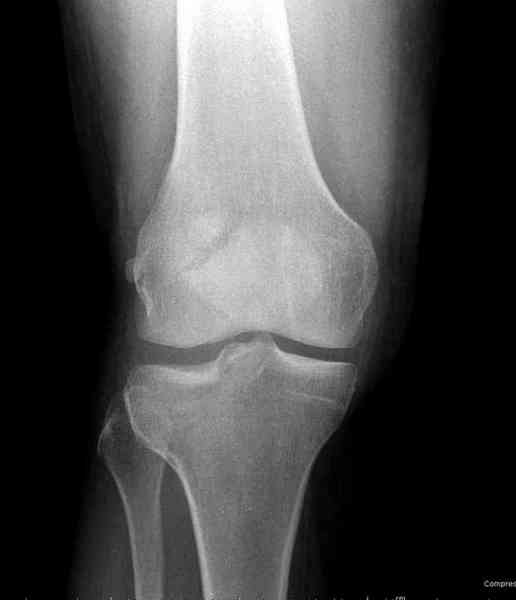

>"мыщелок левой голени будет прооперирован - репозиция, синтез пластиной с костной пластикой, при необходимости удаление повреждённой части мениска"

Для внутрисуставных переломов необходимо идеальное сопоставление, а такая задача без КТ срезов усложнится. Только КТ надо делать после дистракции сустава, иначе нельзя получить объективную информацию.

Около 60% переломов тибиал плато характеризуются мягкоткаными повреждениямм - разрывы суставной капсулы, связок и менисков. Мениск повреждается спереди со стороны перелома.

Тактику удаления мениска во время восстановления считаю ошибочной, наоборот, всеми путями надо его сохранить, потому что предупреждает от деформирующего артроза.

"Removal of a meniscus during the fracture surgery resulted in secondary degeneration in 74% of the cases. When a meniscus was intact or repaired, the proportion of degenerative cases was only 37%. Normal or slight valgus alignment of the tibial plateau with intact menisci protected best against secondary degeneration. On the other hand, medial or lateral tilt of the tibial plateau with a removed meniscus was followed by osteoarthritis in most cases. Honkonen SE., J Orthop Trauma. 1995"